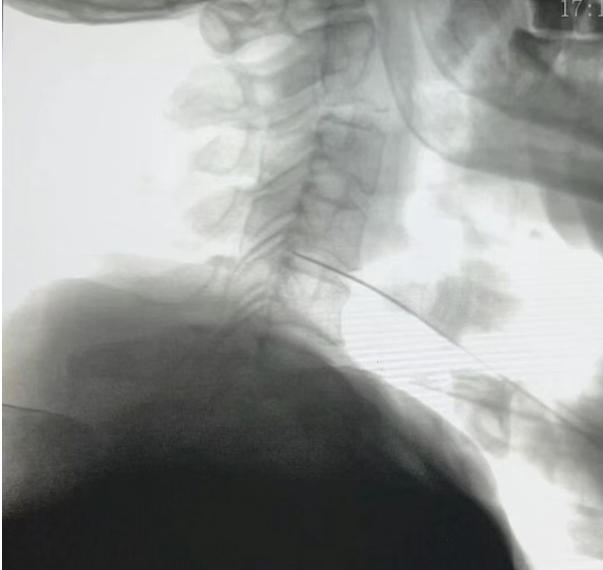

颈椎间盘射频消融联合胶原酶化学溶解术后